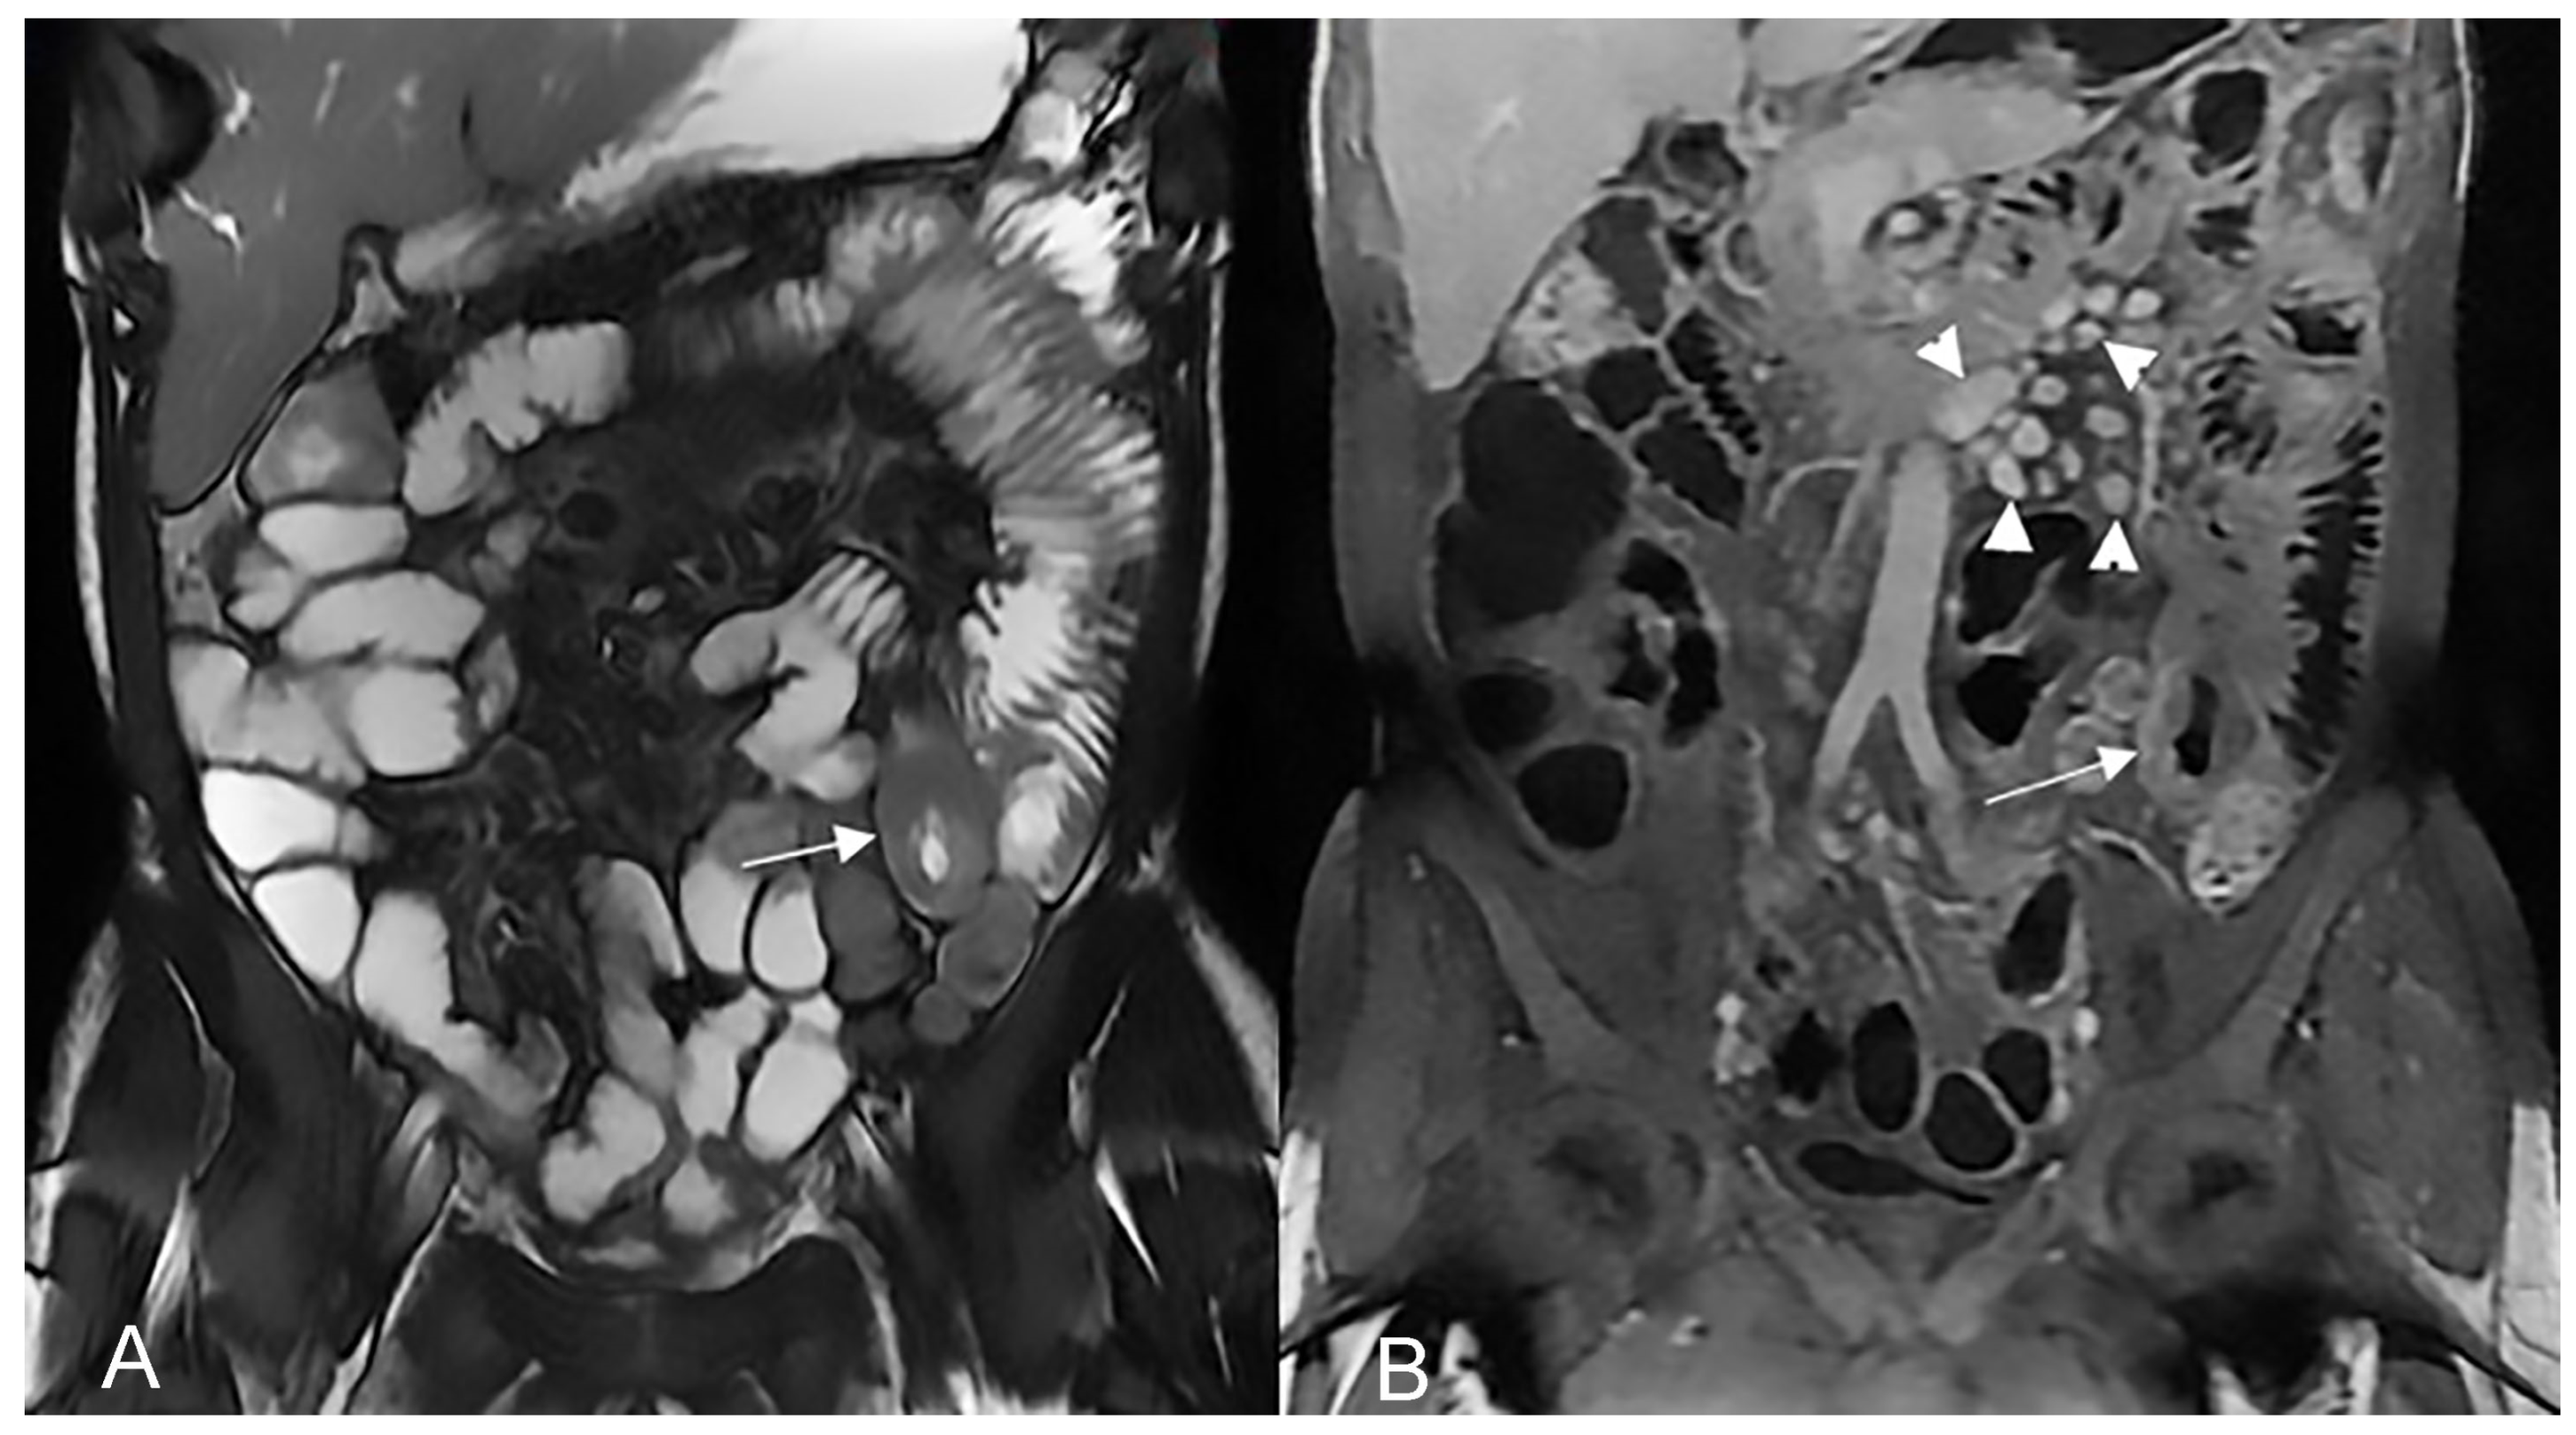

Figure 12.

Inflammatory conglomerate represents a climbing mesenteric fat involvement in the context of penetrating disease and mesenteric inflammation. The components of the fistulas within the mass can be difficult to detect because it often coexists with phenomena of retraction that are expressed on the intestinal loops nearby or on the ureters. Small inflammatory conglomerate in the context of the mesentery adherent to a segment of the pathological small intestine, with active disease (yellow arrowheads in (A,C): coronal (A) and axial (C) contrast-enhanced fat-suppressed T1-weighted image and in (B,E) (coronal fast imaging employing steady-state acquisition; FIESTA image) and (D) (coronal T2-weighted MRE image)).

An abdominal phlegmon is an obsolete term that refers to an inflammatory mass that can develop in the setting of penetrating Crohn’s disease. The term phlegmon is ambiguous and relates to an ill-defined inflammatory dense mesenteric mass. It typically spreads without a well-defined wall and involves the mesentery and adjacent bowel with fistula or abscess as possible complication [12]. Inflammatory conglomerate is the accurate terminology to use in the radiological reports. On MRE images, it appears as a variable signal intensity mixed with fat, usually associated with signs of penetrating disease such as complex fistulas [5] (Figure 12, Figure 13 and Figure 14).